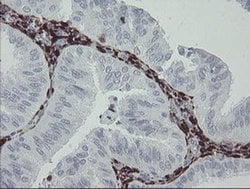

F13A1 Monoclonal Antibody (OTI3F1), TrueMAB™, OriGene

Immunohistochemistry (Paraffin), Western Blot